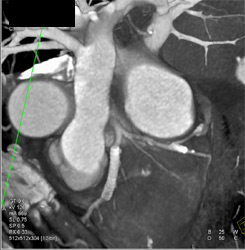

Patent Stent in LAD